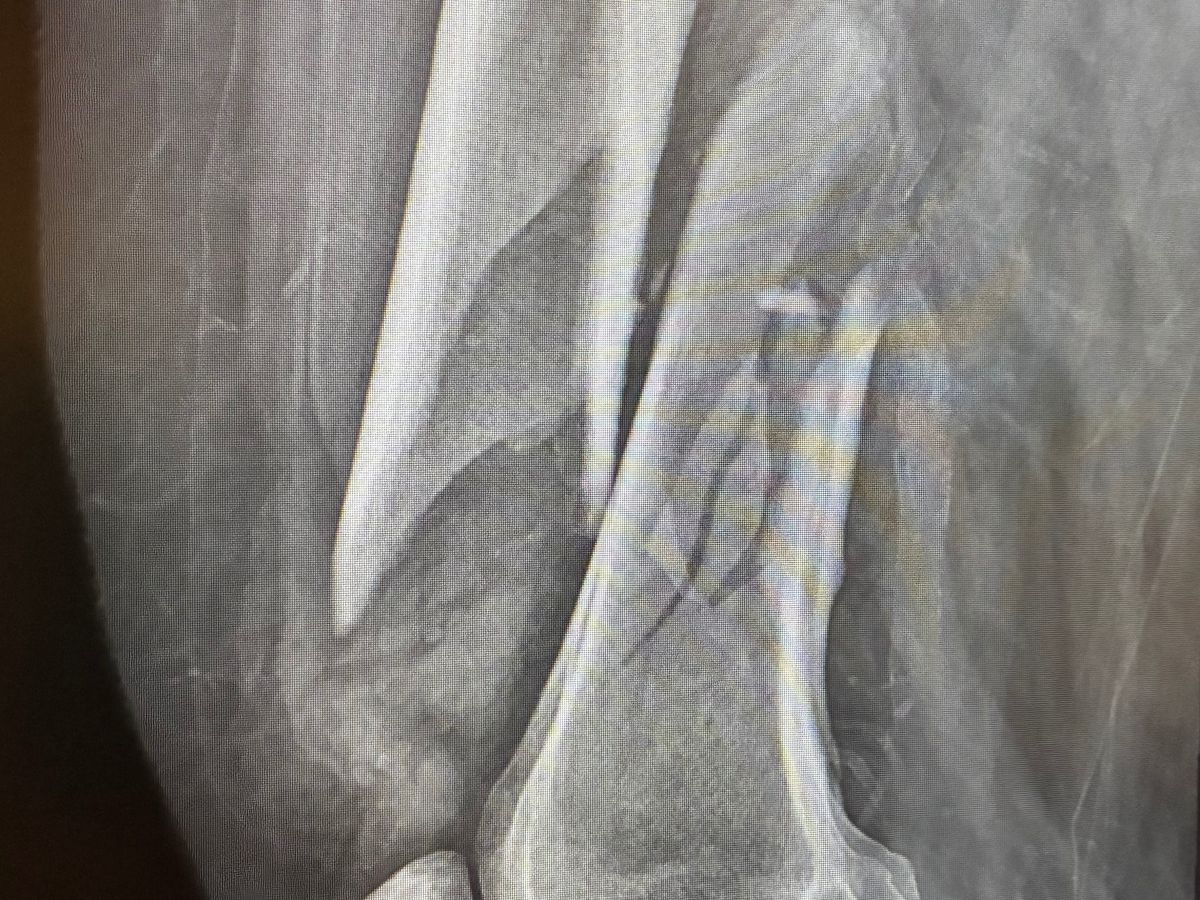

In mid October of 2025 I fell and broke my right femur and had to have surgery to place a metal rod and screws in my leg. I have been in physical rehabilitation since my surgery. The recovery period for a broken femur is long and I have made significant progress however I still can not walk. I exhausted my Medicare days available for rehabilitation and I'm in danger of being sent home unable to walk. I'm right on the verge of walking again but I need to raise money to pay out of pocket for my remaining therapy needs. The cost is $270 a day and I need about 3 more weeks in therapy. I'm trying to raise $6,000 to cover these expenses. Anything you're able to give will be greatly appreciated. Thank you.